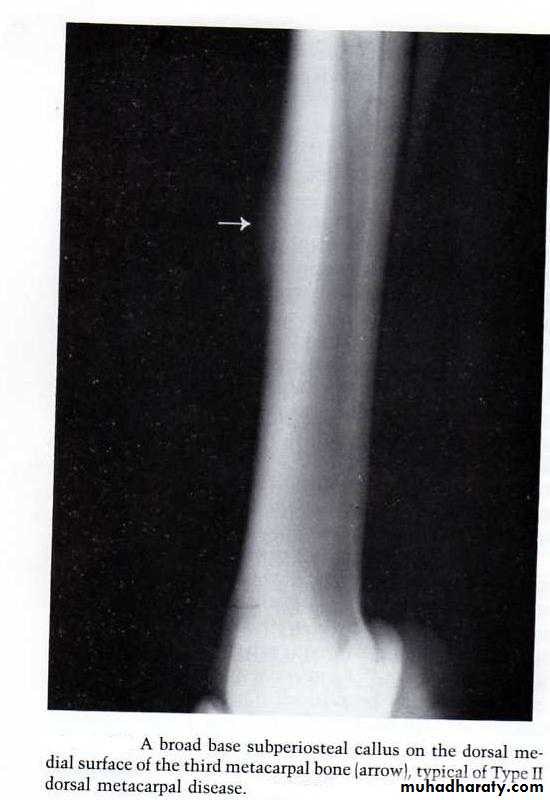

On radiographic examination a subperiosteal callus is usually observed.

A broad base subperiosteal callus on the dorsal medial surface of the third metacarpal bone (arrow) typical type 2 dorsal metacarpal disease.